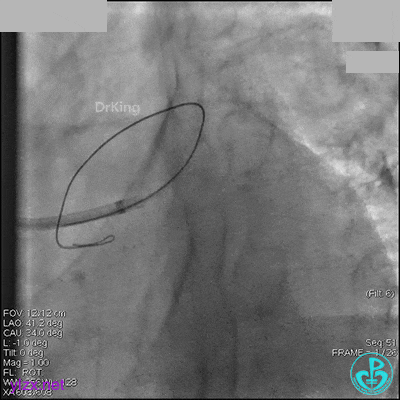

右冠脉中段充分扩张后欲植入3.5×38mm支架时,支架难以通过中远段扭曲处,且指引导管、导丝弹出飞扬。反复尝试导丝重新到达右冠脉远端时通过不顺利,局部造影剂滞留,远端血流接近3级。

右冠脉血流3级,患者无症状,终止手术。